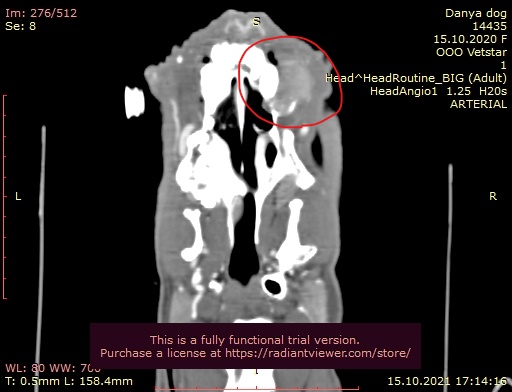

Причина обращения: образование на верхней челюсти, боль при приеме пищи, кровянистые выделения изо рта и неприятный запах изо рта, ассиметрия морды (изоб.1). В сторонней клинике проводили инцизионную биопсию, морфологический диагноз – плоскоклеточный рак.

Изображение 1

Отмечается частичный лизис кости верхней челюсти справа в зоне клыка и премоляров. В постконтрастную фазу отмечается очаговое образование с накоплением контраста в области верхней челюсти справа (зона клыка и премоляров) размером 17 х 25 х 17 мм. Отмечается незначительная инвазия опухоли в правый носовой ход (изоб.2).